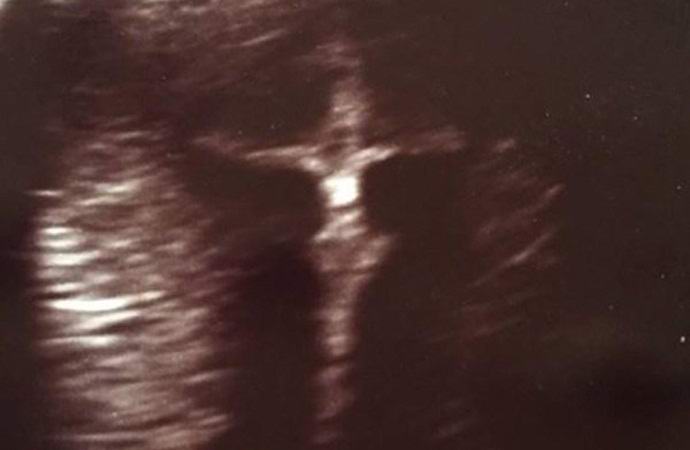

Noseča Američanka Eli Meyer, ki je potekala sredi oktobra ultrazvočni pregled ploda. Niti bodoče ženske v porodih niti ne uslužbenci Centra za zdravo materinstvo med tem niso opazili Postopek ni nič nenavadnega. Izkazalo se je, da Meyer pričakuje fanta, vendar so bili vsi kazalci otrokovega zdravja normalni. Samo teden dni kasneje je eden od Elijevih prijateljev žensko opozoril na čuden detajl, ki se kaže v sonografiji njenega ploda.

Meyer, ki živi s svojim možem v Evansvillu Vendar Indiana še nikoli ni bila religiozna oseba bodoča mati načrtuje, da bo ponovno preučila svoj odnos do vere v Boga. Dejstvo je, da se je na ultrazvoku Meyer sprva vtisnil čudno poglej, “artefakt” presenetljivo podoben križanju z Jezusom Po Kristusu. Na sliki sta jasno vidna križ in tanek dolgodlaki moški, ki visi na njem. V to so prepričani tudi Eli, pa tudi njen mož in prijatelji to je znak od zgoraj, in to ne samo za Američanko, ampak tudi zanjo še ne rojen sin, ki je bil pred kratkim enaintrideset na teden.

Ko je noseča mati Meyer izvedela za to skrivnostno incidenta, je podobo Odrešenika objavila v družabnem Facebook, kjer je neverjeten posnetek pritegnil pozornost tisočev uporabnikov in se takoj širijo na druga spletna mesta. Mnogi Omrežni redarji pravijo, da ne morejo zanikati neverjetnega podobnost “artefakta” s križanjem z Božjim sinom. “Če to in naključje, potem se taka naključja zgodijo enkrat tisočletja, “- zapiše en komentator. “Morda je to znak, da otroka čaka nenavadno življenje, “predlaga drugo.” na tem svetu se ne zgodi nič, “doda tretjina.

Nosečni ginekolog dr. Michael Broder trdi, da “slika križa” je pravzaprav razvijajoča se osrednja točka fetalni živčni sistem. Vendar to ne nasprotuje bistvu pogled na tiste, ki so na tej sliki videli čudež. Zdravnik in on sam potrjuje, da za svojo prakso nikoli ni videl ničesar takšen. “Seveda smo prepričani, da je to osrednje živce otroškega sistema, vendar je vseeno vredno priznati, da to res zelo podoben križanju, «se strinja Broder.